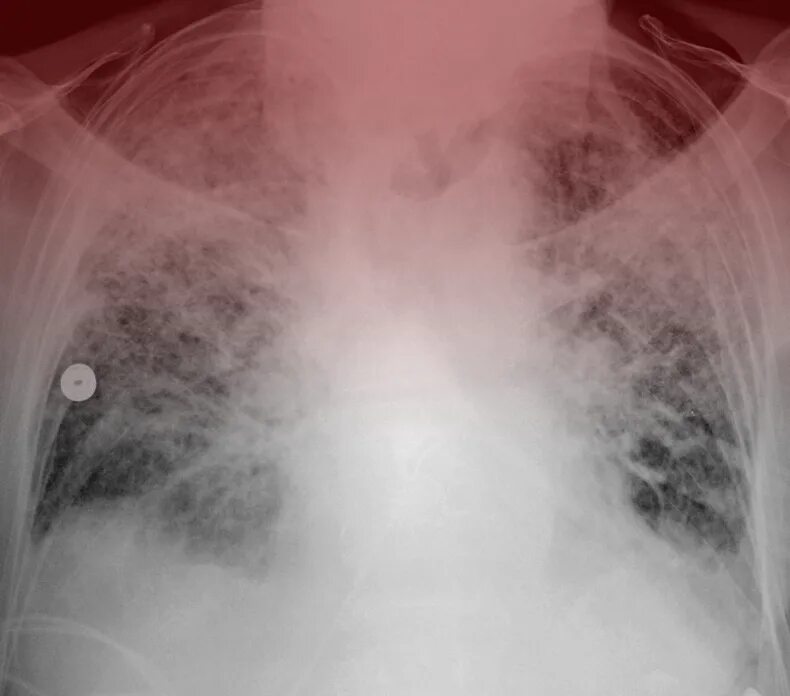

Ордс крипта